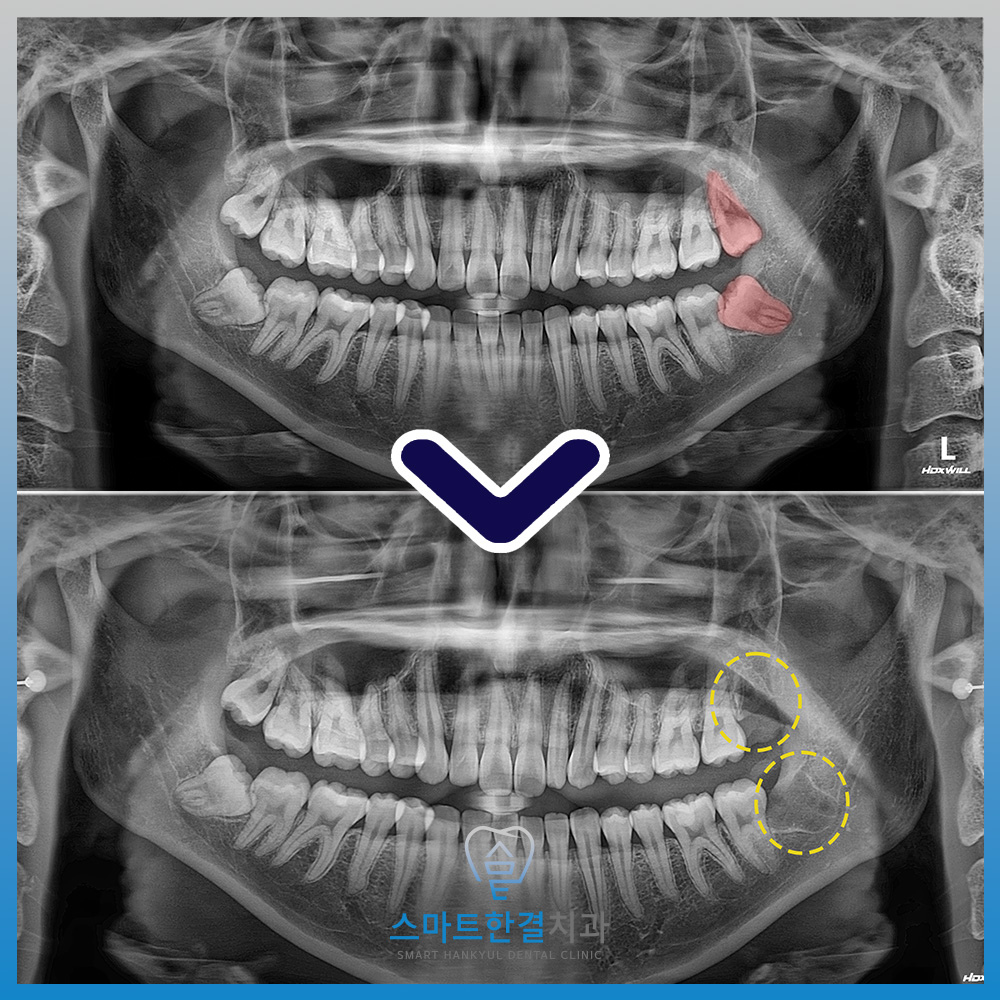

파노라마 사진에서는

왼쪽 아래 사랑니가 잇몸 안에 묻혀 있으면서

앞 치아 쪽으로 비스듬히 누워 있는

모습이 확인되었어요.

<수술적으로 사랑니 발치>

왼쪽 위, 아래 2개의

사랑니를 발치한 모습이에요.

또한, 사랑니의 뿌리와 신경관이

파노라마 사진에서 중첩되어 확인되어,

발치 전 3D CT 촬영을 통해 정밀하게 분석한 후

안정적으로 발치를 진행하였답니다. (^^)